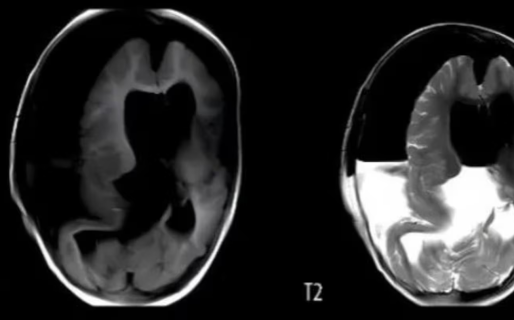

Una nena de un año tuvo que ser hospitalizada debido al gran tamaño de su cráneo y a que presentaba retrasos en sus habilidades motoras. Una vez internada le realizaron una tomografía que reveló que tenía un “tejido blando, hueso similar al de las extremidades y sombras de tejido óseo mixto en el área intracraneal”. Le realizaron una craneotomía y descubrieron que tenía un feto creciendo en su cabeza.

En el caso de esta beba, los médicos detectaron anomalías en su cráneo a las 33 semanas de gestación, durante un examen prenatal. Pero, la resonancia magnética no pudo proporcionar más información. La beba nació por cesárea a la semana 37 y los médicos notaron que su cabeza era notablemente más grande que lo normal.

Tras de la craneotomía que le realizaron, los médicos indicaron: “Extrajimos un embrión inmaduro, con vérnix y órganos visibles, como la boca, los ojos, la cabeza fetal, el pelo fetal, el cuerpo, el antebrazo, las manos y los pies”. A su vez, detallaron que el embrión medía 18 cm de largo, tenía rasgos y extremidades malformadas, así como huesos largos y una columna vertebral.